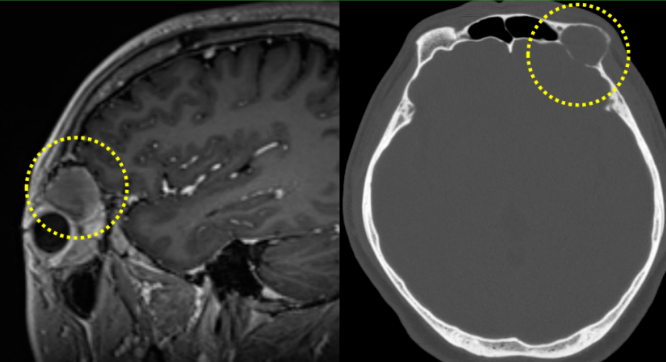

患者江先生(化名)两个月前发现左眼逐渐外凸,容貌变化让他心生不安,随即前往中国医科大学附属第一医院眼科孙一洲副教授门诊就诊。孙一洲详细查体并结合核磁共振检查后,确诊患者左眼眶内存在占位性病变,具备明确手术指征。影像显示,病变已破坏颅底骨质并累及硬脑膜,肿瘤已从眼眶“跨界”侵入颅内。这种特殊的生长位置,给手术带来极大挑战,若处理不当,术后极易出现脑脊液漏、颅内感染等严重并发症。

患者术前影像,黄线内示肿物